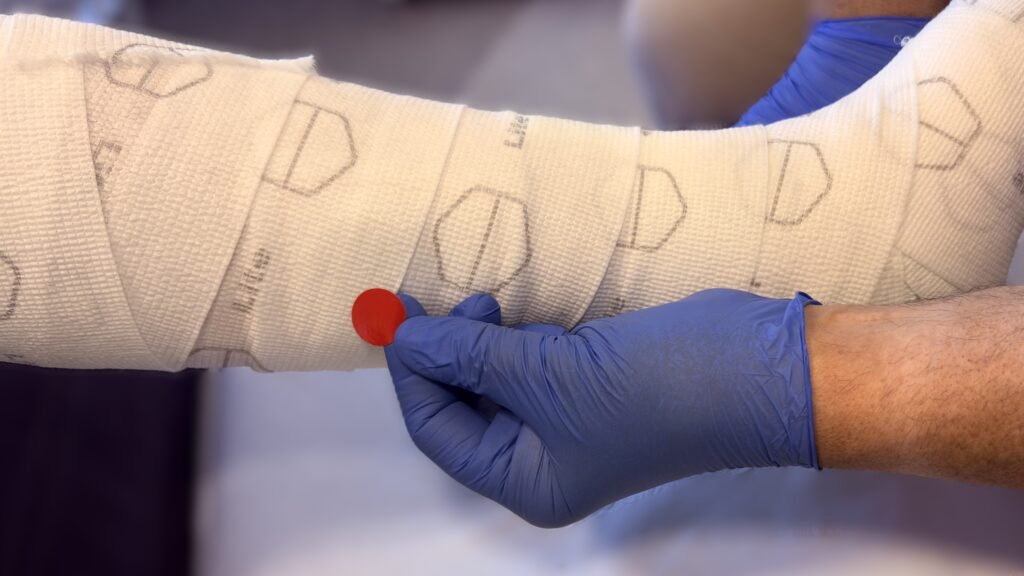

Sorbalgon Classic

Sorbalgon T Classic